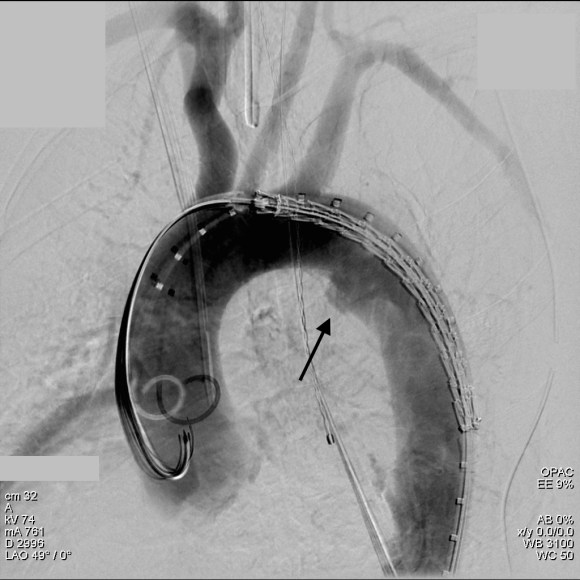

The common femoral endarterectomy is done from its distal most point and the Vollmer ring is used to mobilize the plaque. A Moll Ring Cutter (LeMaitre Vascular) is then used to cut the plaque.

The plaque is extracted and re-establishes patency of the EIA.

The plaque end point is typically treated with a stent -in this case, the common iliac plaque was also treated.

What is nice about this approach is that this artery has been restored to nearly its original condition. I have taken biopsies of the artery several months after the procedure in the process of using the artery as inflow for a cross femoral bypass, and the artery clamped and sewed like a normal artery and the pathology returned normal artery.

This has several advantages over conduit creation which can be a morbid and high risk procedure in patients who require minimally invasive approach. A graft is avoided. The artery is over 8mm in diameter where with stenting up to 8mm with an occlusive plaque, the danger of rupture is present, and often ballooning is restricted to 6mm-7mm. This is insufficient for many TEVAR grafts and TAVR valves.